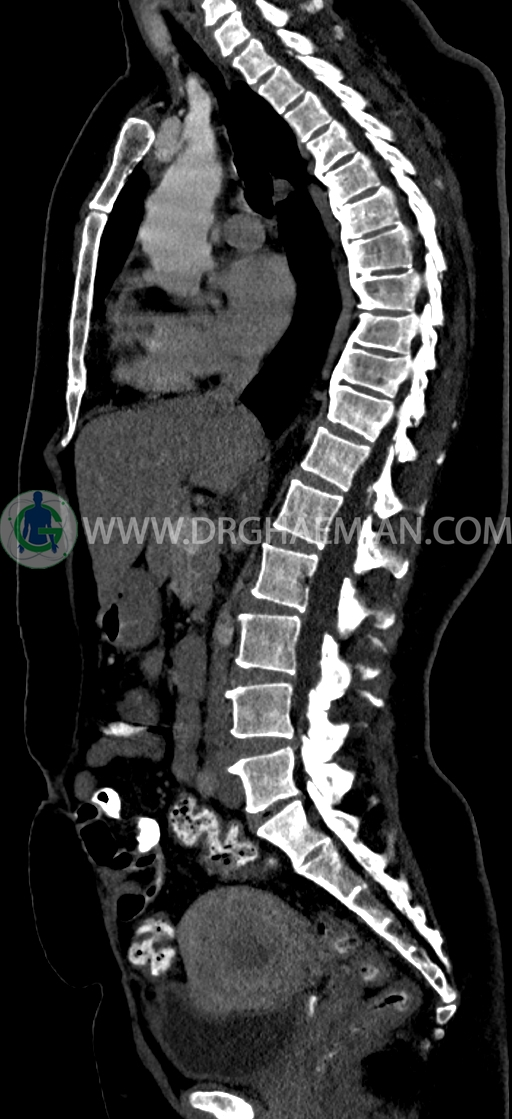

–Bridging osteophyte در مهره هاي توراسيک مطرح کننده DISH همراه با کيفوز مشهود است.